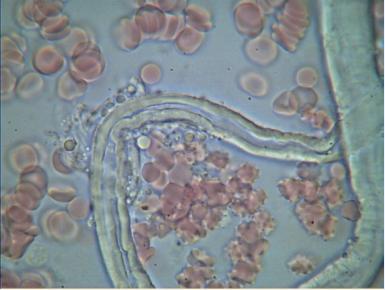

2.PASOŻYTY I GRZYBY

w zakwaszonym środowisku rozwijają się różnego rodzaju organizmy pasożytujące : robaki, grzyby, bakterie, wirusy i inne. Walka z nimi jest możliwa tylko przez zmianę środowiska z kwaśnego na zasadowe, w tym środowisku nie mogą się one rozmnażać i żyć.

We krwi widoczne są larwy i jaja pasożytów.